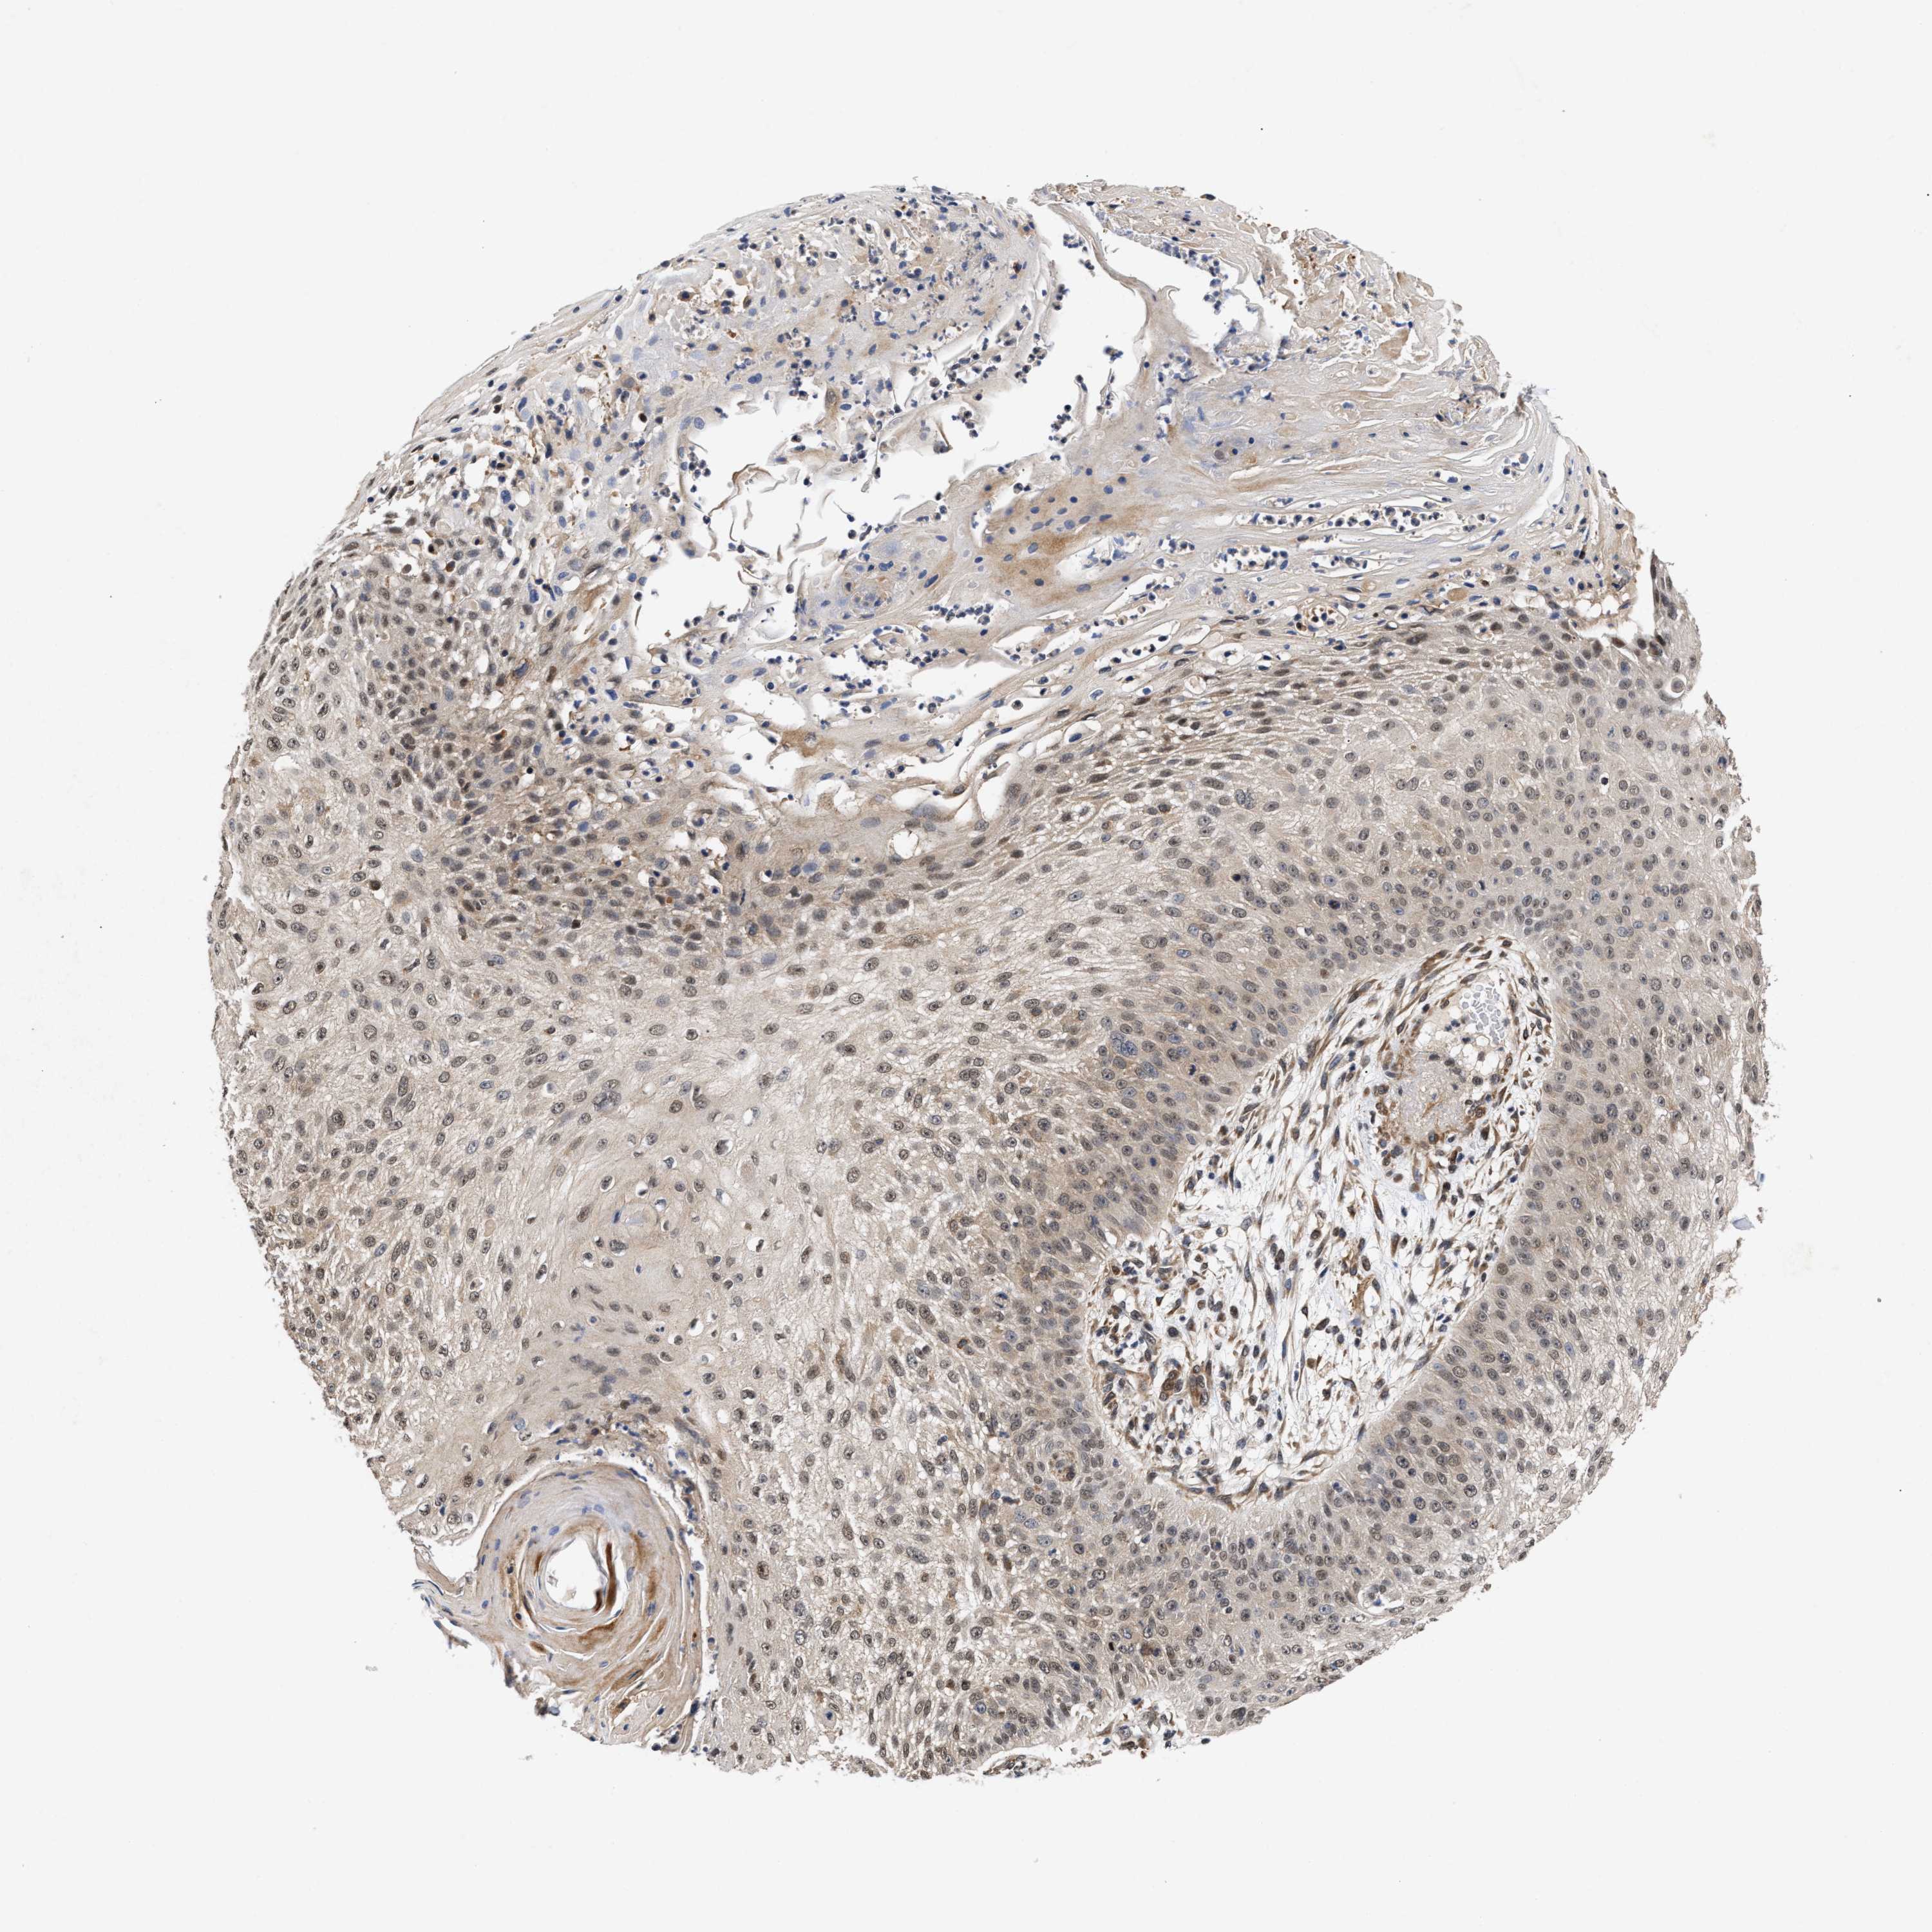

SKIN CANCER - Protein expressioni

A mouse-over function shows sample information and annotation data. Click on an image to view it in a full screen mode. Samples can be filtered based on level of antibody staining by selecting one or several of the following categories: high, medium, low and not detected. The assay and annotation is described here.

Antibody stainingi

Antibody staining in the annotated cell types in the current human tissue is reported as not detected, low, medium, or high, based on conventional immunohistochemistry profiling in selected tissues. This score is based on the combination of the staining intensity and fraction of stained cells.

Each image is clickable and will lead to virtual microscopy that enables deeper exploration of all samples and also displays staining intensity scores, fraction scores and subcellular localization as well as patient and tissue information for each sample.

Antibody CAB020767

Staining

High

Medium

Low

Not detected

Intensity

Strong

Moderate

Weak

Negative

Quantity

>75%

75%-25%

<25%

None

Location

Nuclear

Cytoplasmic/membranous

Cytoplasmic/membranous,nuclear

Squamous cell carcinoma in situ, NOS

Squamous cell carcinoma, NOS

Squamous cell carcinoma, metastatic, NOS

Basal cell carcinoma